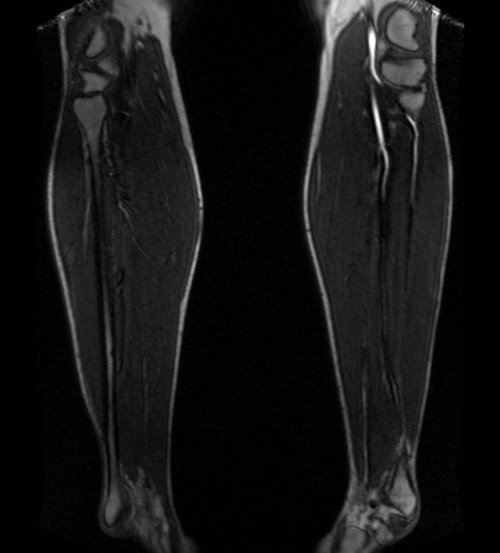

LOWER LEG